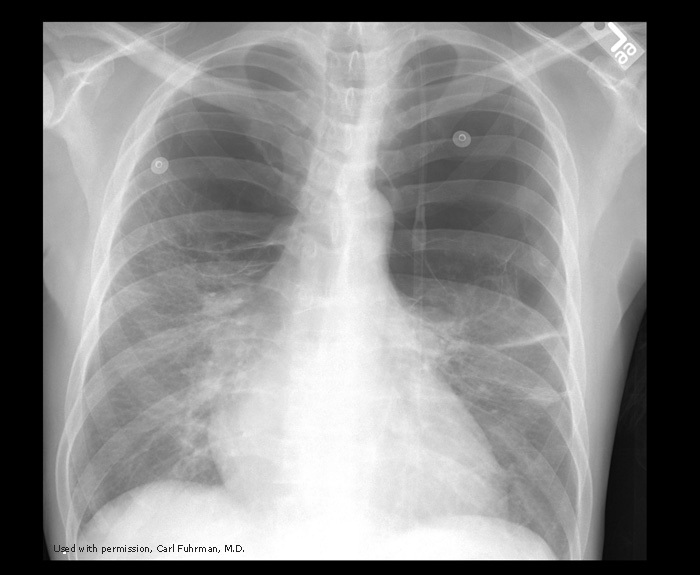

What is going on in this CXR?

These radiographs show atelectasis of the right middle lobe

You can tell that this is atelectasis rather than a consolidation by the downward displacement of the minor fissure

Fissures move towards a collapsed lobe, as do the trachea and heart, and the ipsilateral diaphragm.